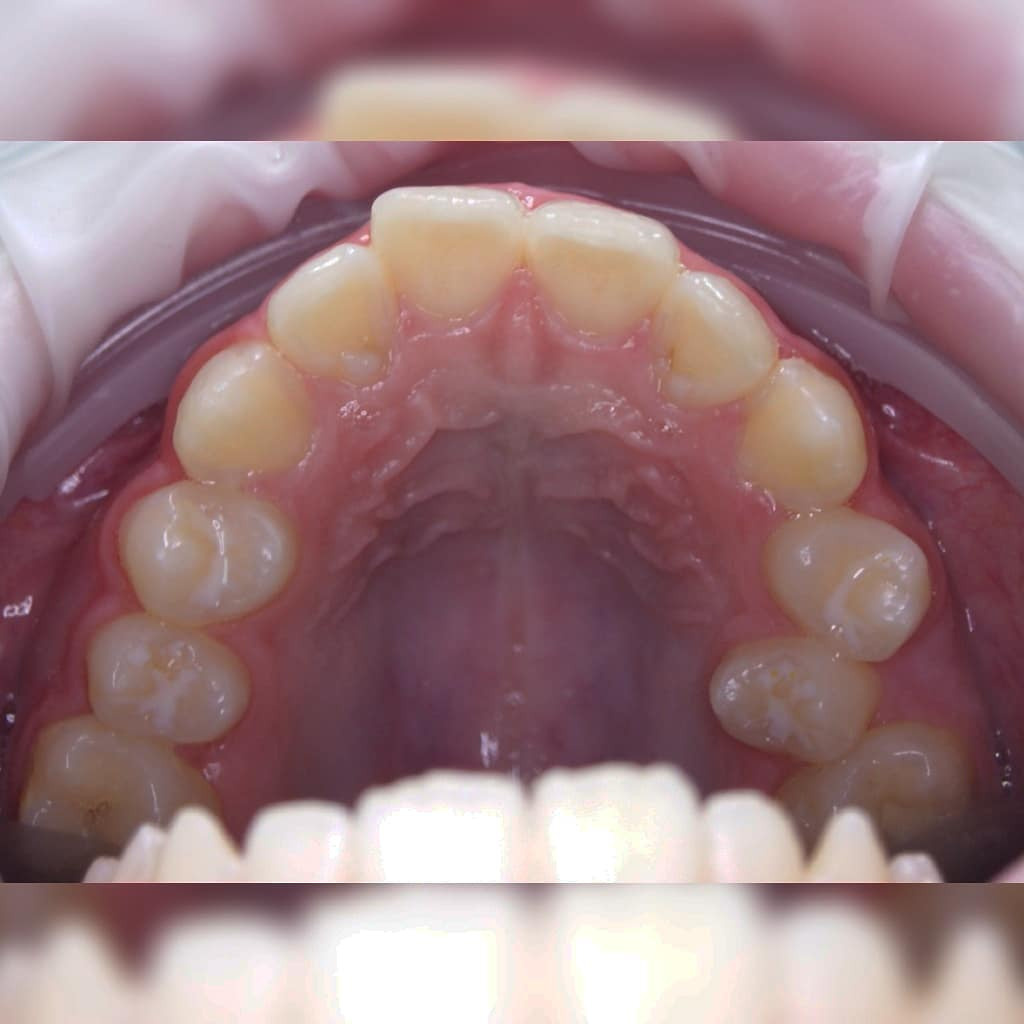

Эта фраза знакома многим ответственным родителям, которые привели на приём к ОРТОДОНТУ своего ребёнка в 5-10 лет, заподозрив проблему или понимая, что места постоянным зубам откровенно не хватает! Горькая правда в том, что брекеты - не волшебное средство от всех проблем, они "расставляют" зубы внутри сформированого объёма челюсти, но никак не влияют на её рост. Родители ждут, а тем временем драгоценное время, когда ребёнок растёт, уходит... Во взрослом возрасте приходится удалять здоровые зубы или прибегать к ортогнатической хирургической операции. 📸 На фото узкая нижняя челюсть, места постоянным зубам нет, боковые резцы прорезываются "вторым рядом".

🔷️ Промежуточный результат лечения на аппарате Марко Роса (6 месяцев). Пациенту 7 лет. Самое удивительное - как "отвечает" на лечение нижняя челюсть: расширяется, меняется её положение и корректируется дистальный прикус, выравниваются нижние зубы, хотя никаких аппаратов на нижней челюсти не было!

❓Почему на нижней челюсти зубы тоже прорезываются неровно?

▶️ При сужении верхней челюсти сужается и нижняя, так как нижняя под верхнюю "подстраивается". Верхняя челюсть словно зажимает в тиски нижнюю челюсть и тормозит её рост.

❓Нижнюю челюсть тоже нужно расширять?

▶️ При достаточном расширении верхней челюсти, нижняя начинает "расти" и "подстраиваться" под верхнюю сама. Такая адаптация может занять год. Но часто мы помогаем расширению нижней челюсти (дополнительные аппараты, гимнастика для мышц лица и рта, др.)